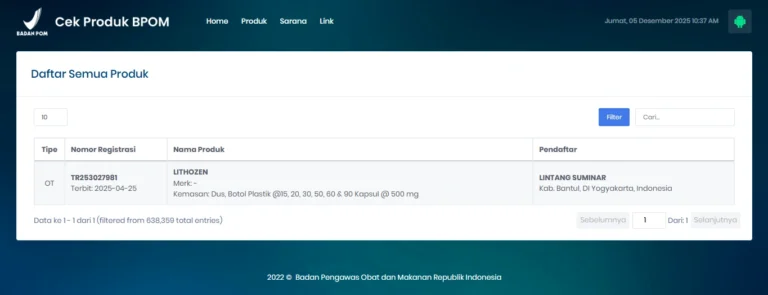

Terdaftar BPOM